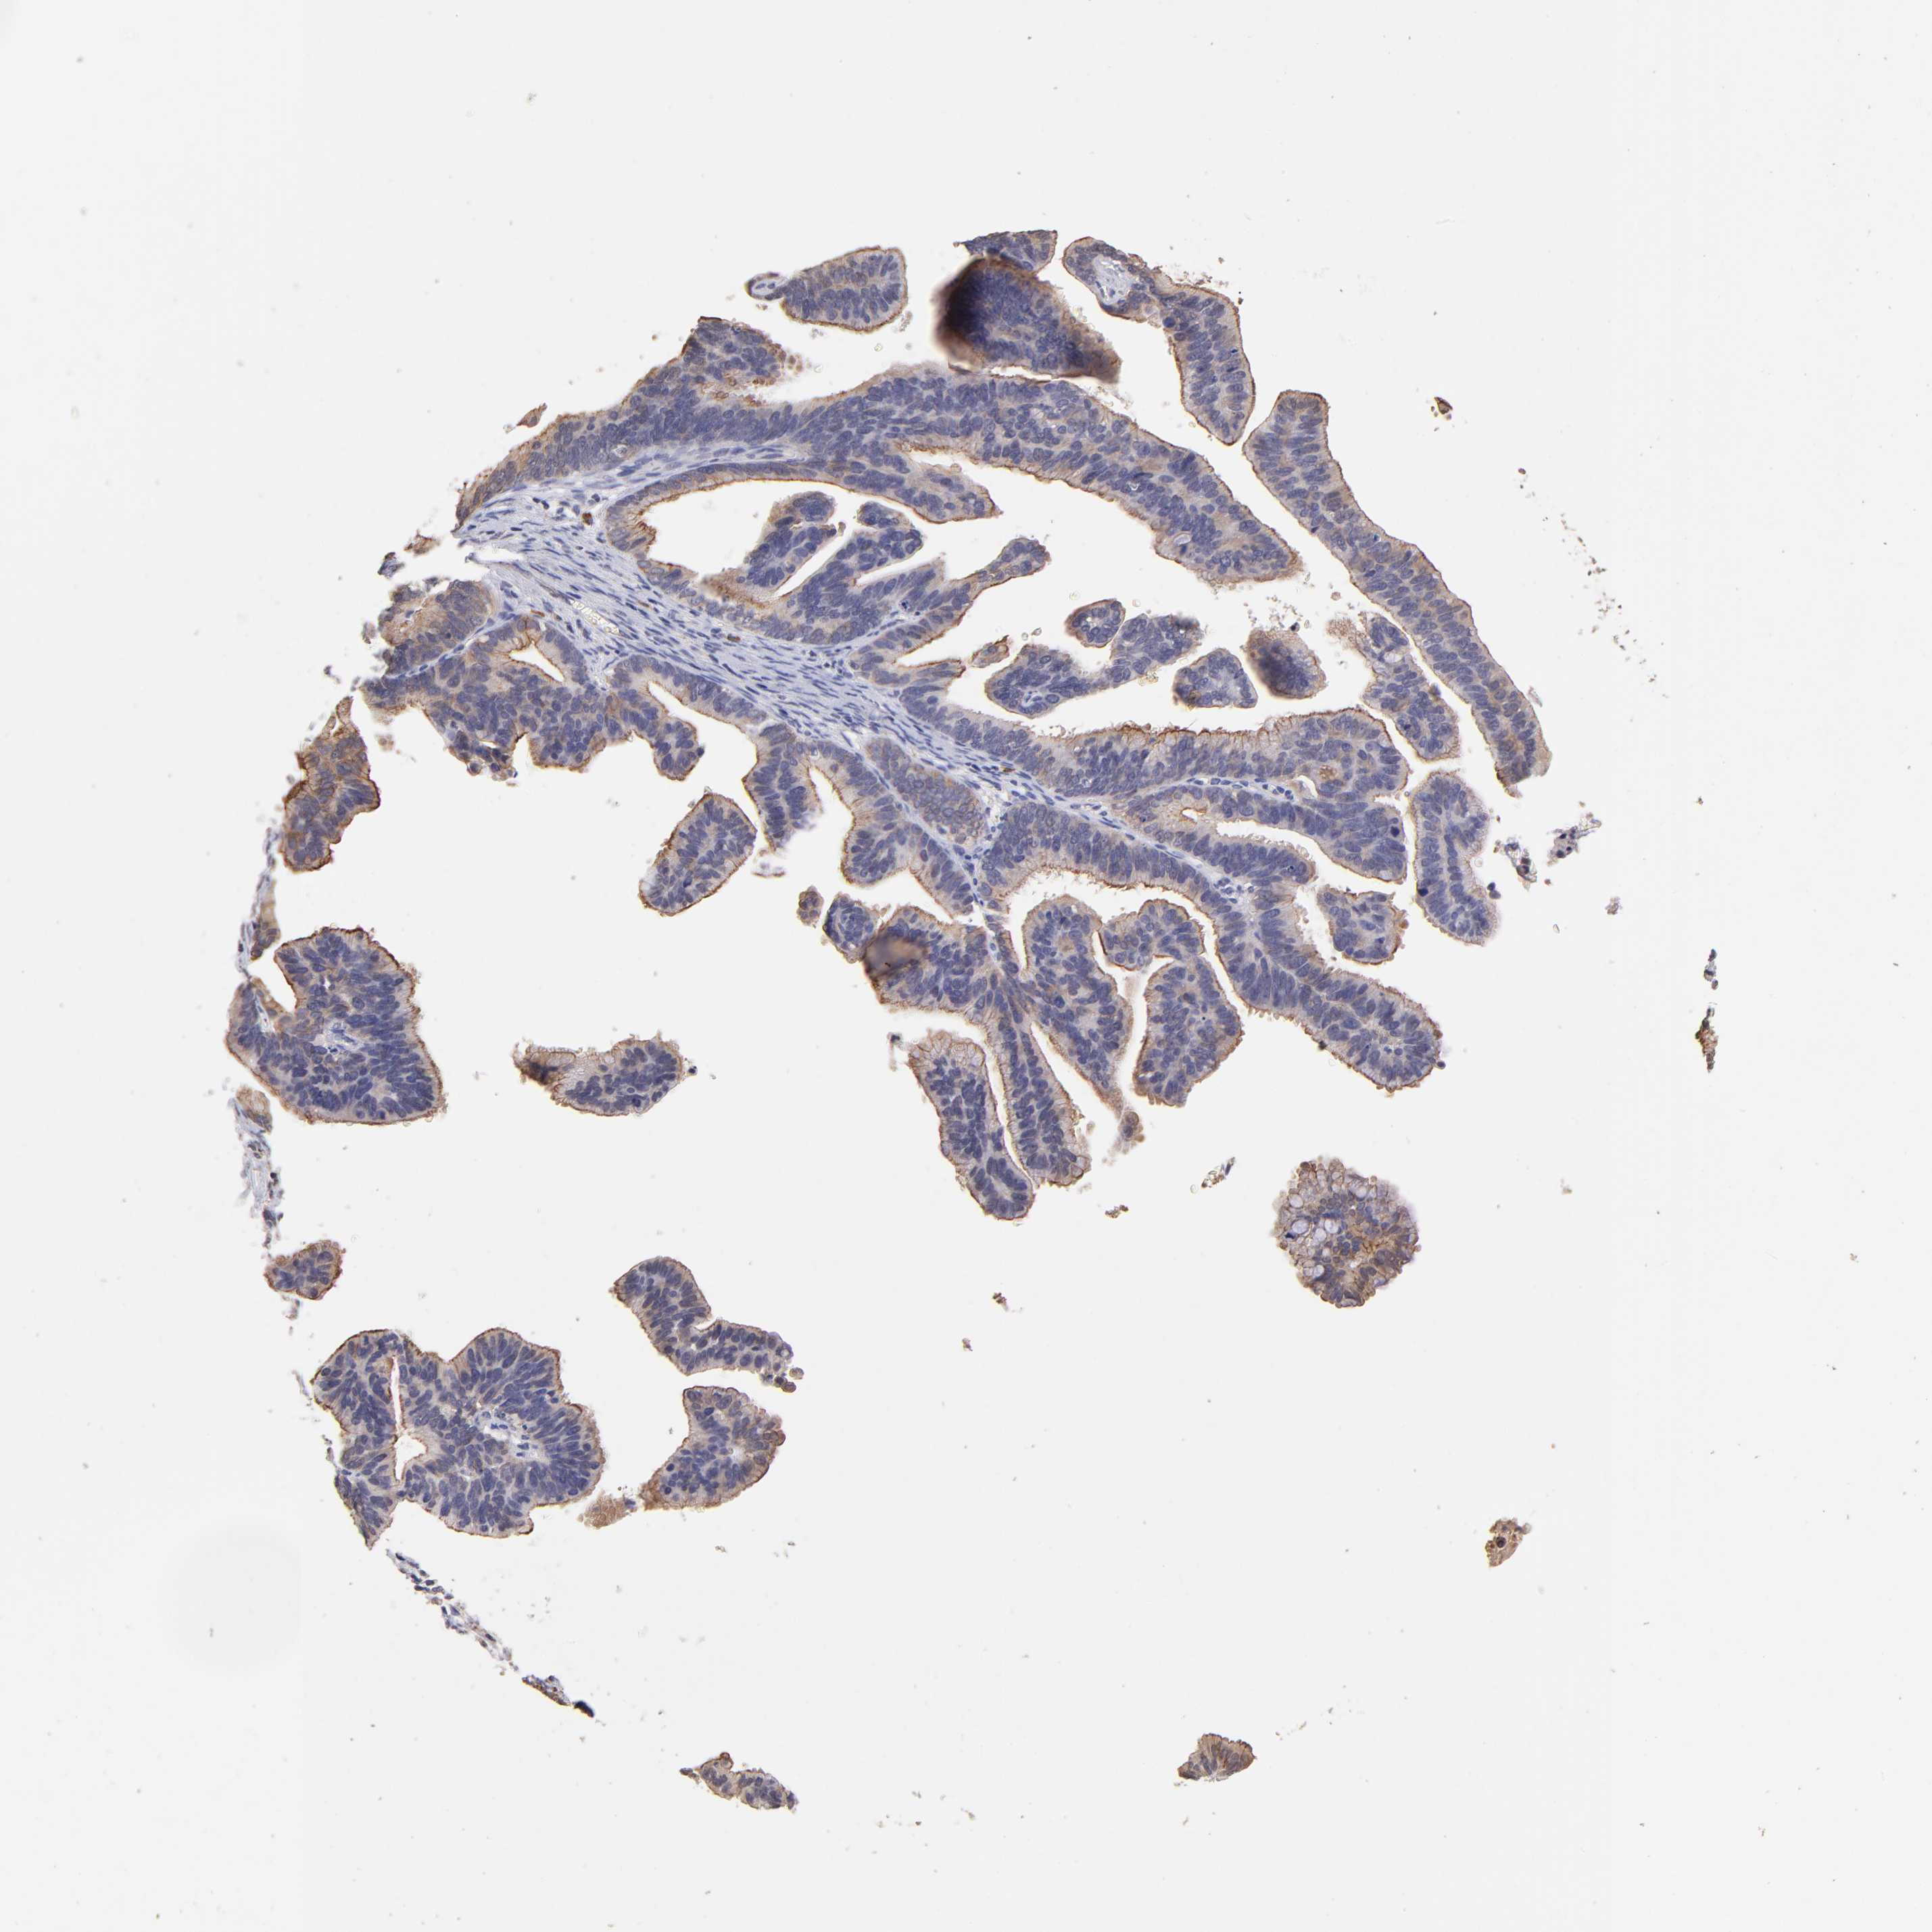

CERVICAL CANCER - Protein expressioni

A mouse-over function shows sample information and annotation data. Click on an image to view it in a full screen mode. Samples can be filtered based on level of antibody staining by selecting one or several of the following categories: high, medium, low and not detected. The assay and annotation is described here.

Note that samples used for immunohistochemistry by the Human Protein Atlas do not correspond to samples in the TCGA dataset.

Antibody stainingi

Antibody staining in the annotated cell types in the current human tissue is reported as not detected, low, medium, or high, based on conventional immunohistochemistry profiling in selected tissues. This score is based on the combination of the staining intensity and fraction of stained cells.

Each image is clickable and will lead to virtual microscopy that enables deeper exploration of all samples and also displays staining intensity scores, fraction scores and subcellular localization as well as patient and tissue information for each sample.

Antibody HPA002633

Antibody HPA046758

Adenocarcinoma, NOS

Squamous cell carcinoma, NOS